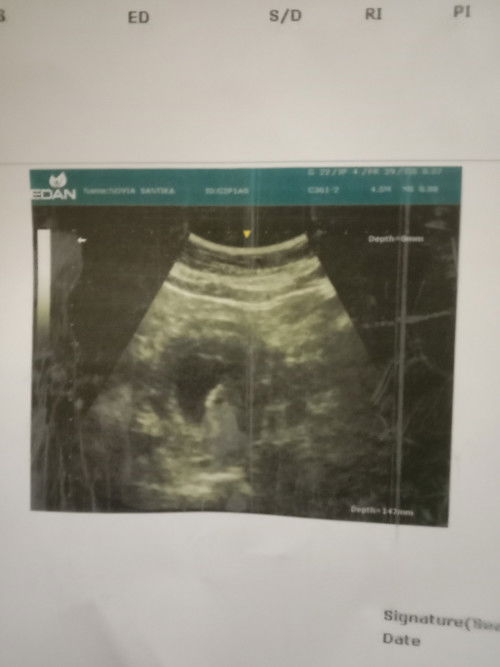

Usg 9 week 3d

Bun mau t? Donk ada gk yng sama kyk saya Kmaren awal USG 8week janin blom keliatan baru kantong nya saja setelah 9week 3d saya usg lgi janin sudah jelas terlihat tpi djj nya blom terdeteksi bidan nya nyaranin saya usg transvaginal ,gimana ya bund apa saya hrus menunggu seminggu lgi apa lngsung transvaginal